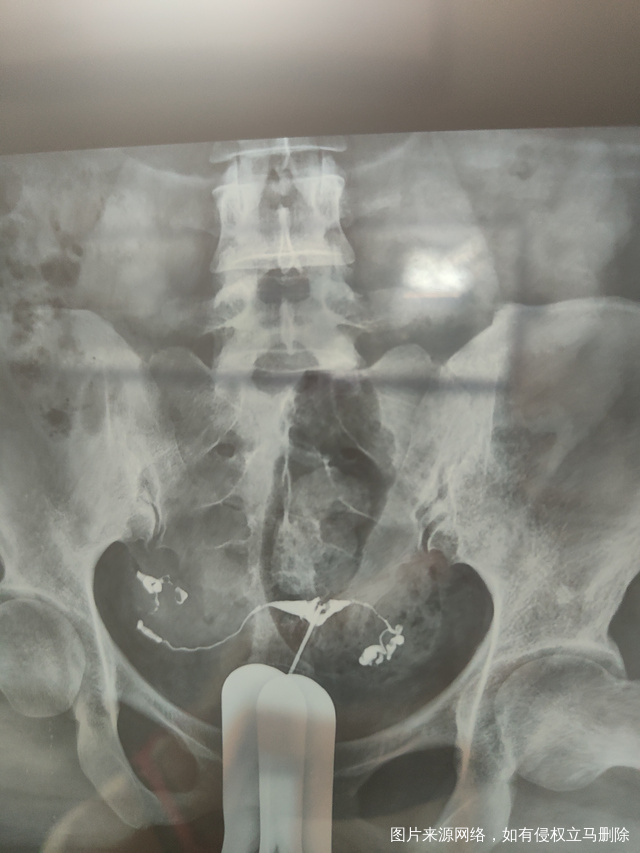

各位医生好前天做了输卵管造影请帮忙看看这些造